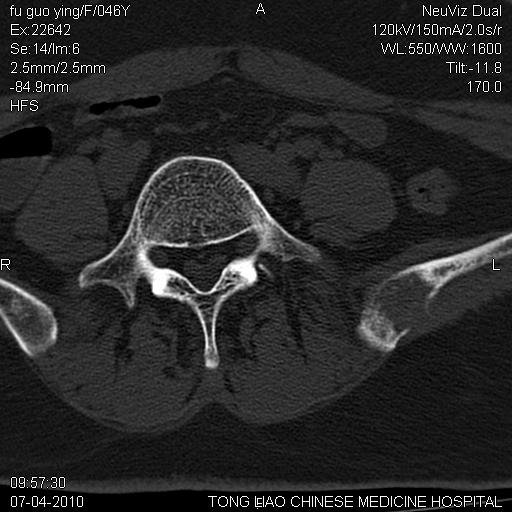

标题: CT27489:患者腰疼,其余椎体未见异常! [打印本页]

标题: CT27489:患者腰疼,其余椎体未见异常!

髂骨考虑转移瘤 椎体病变不像转移瘤

女性46岁,左髂骨溶骨性破坏+软组织肿块,考虑转移瘤,腰椎为退变/增生硬化/软骨下骨囊变。